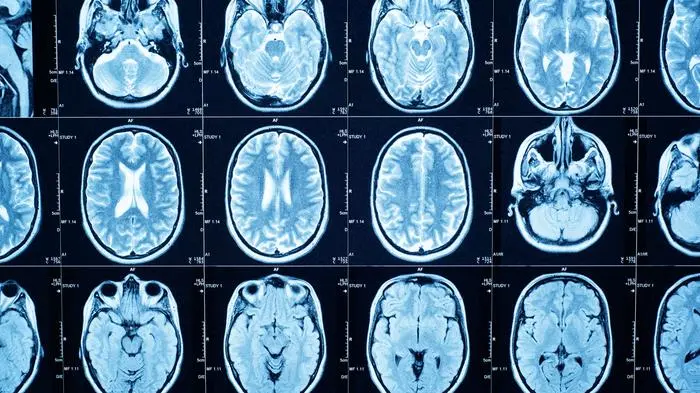

Wie sich unser Gehirn im Laufe unseres Lebens erneuert

Erwachsen sind wir, in Bezug auf unser Gehirn, erst mit etwas über 30 Jahren. Ganz grundsätzlich verläuft die Entwicklung unseres Gehirns in fünf Phasen – es ist ein ständiger Umbau im Gange.

Die Neuverdrahtung des Gehirns verläuft in fünf Phasen